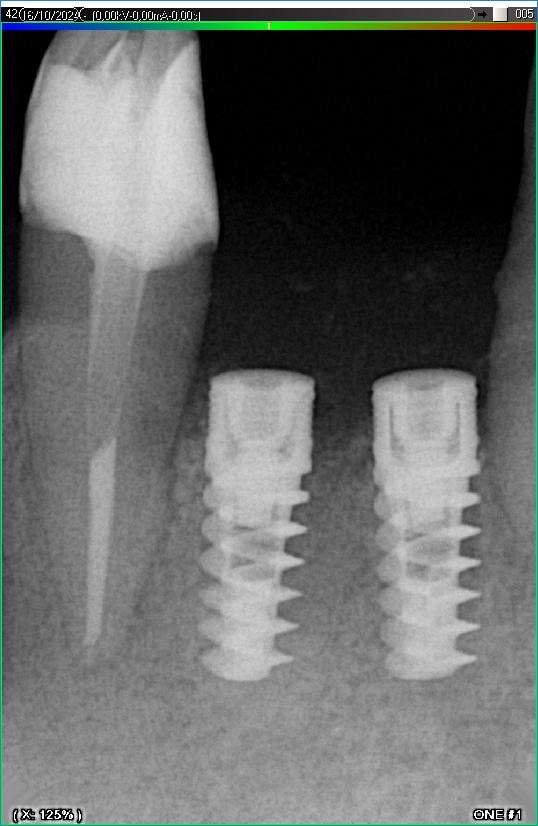

Імплантація